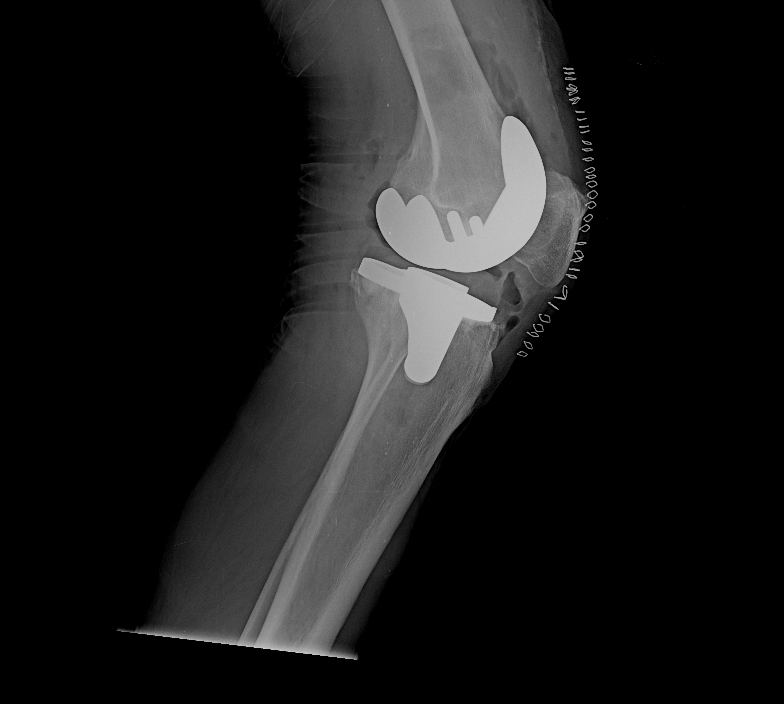

Η ολική αρθροπλαστική γόνατος ελάχιστης επεμβατικότητας γίνεται συνήθως με μέση προσπέλαση ή subvastus προσπέλαση, ανάλογα με την προτίμηση του χειρουργού. Με ειδικά εργαλεία-οδηγούς διαμορφώνεται ο μηρός, η κνήμη και η επιγονατίδα ώστε να αφαιρεθεί ο χόνδρος και το υποχόνδριο οστό. Κατόπιν, τοποθετούνται δοκιμαστικές προθέσεις, ώστε να εκτιμηθεί το εύρος κίνησης της άρθρωσης και –αν χρειάζεται- να χαλαρώσουν οι σύνδεσμοι του γόνατος.

Στη συνέχεια, ο χειρουργός τοποθετεί τις τελικές προθέσεις που εφαρμόζουν συνήθως με τη συνδρομή ειδικού ιατρικού τσιμέντου και επιβεβαιώνει τον αρχικό σχεδιασμό. Διενεργείται αιμόσταση και σχολαστικός καθαρισμός του γόνατος, πριν ολοκληρωθεί η επέμβαση με τη συρραφή του χειρουργικού τραύματος.